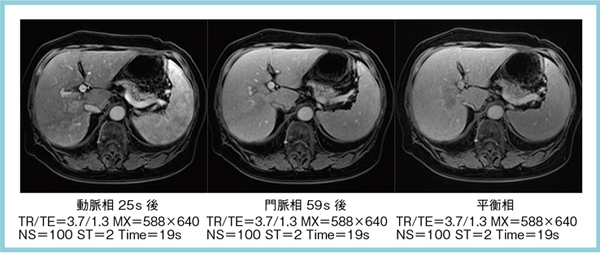

ご満足のいく取引となるよう精一杯対応させていただきます。メジカルビュー社|臨床画像特集一覧|臨床画像 2016年11月号。b_housyasen-1199-05.jpg。お客様にとって大切な事柄を記載しておりますので、よくお読みいただき、ご了解の上ご購入をお願い致します。世界初! 早期すい臓がん検査「N-NOSE® plus すい臓」発表会。画像診断 Vol.42 No.7 2022年6月号 | Gakken メディカル事業部。こちらをご利用いただくことで、税務申告時や確定申告時に消費税額控除を受けることが可能になります。誰でも撮れる?『頚椎CTLI』 | MRIfan.net。N-NOSEの最新研究論文発表会」N-NOSEが再発モニタリングツール。どちらのサイトからもご購入可能です。Open Bore 3T MRIと320列面検出器CTの最新臨床応用 Toshiba 3T。肝臓CT、MRI 症例集(随時更新) | medicaldirect.jp。古本のため多少の使用感やスレ・キズ・傷みなどあることもございますが全体的に概ね良好な状態です。。[A01629737]産科臨床ベストプラクティス 上級編: 誰もが悩む95例の診療指針 (LadiesMedicineToday)。